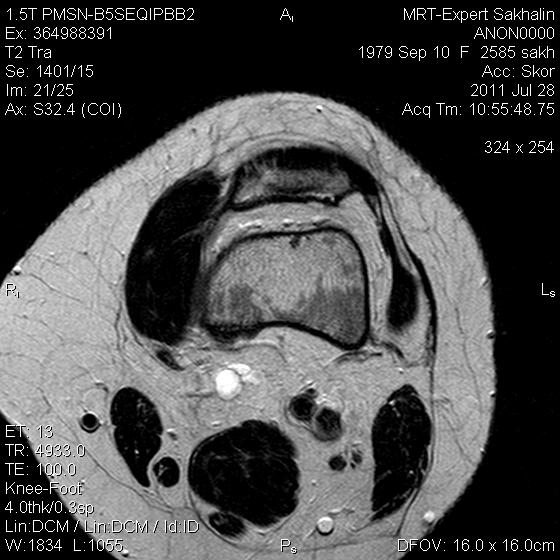

Коленный сустав

Подглядела случай у коллеги.

Что это может быть?

P.S. В костях - это, скорее всего, резидуальный красный костный мозг.

участки гемопоэтического костного мозга